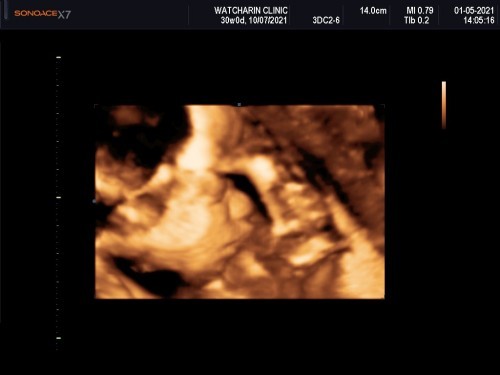

ตอนนี้แม่ท้อง 30 w1d แล้วค่ะ น้องหนักประมาณ 1450 g อยากทราบว่าแม่ๆคนอื่นที่อายุครรภ์เท่ากัน น้องหนักเท่าไรกันคะ.

เมื่อวานไปซาวด์มา30+1นน.น้องได้1384หมอบอก นน.น้องปกติค่ะ